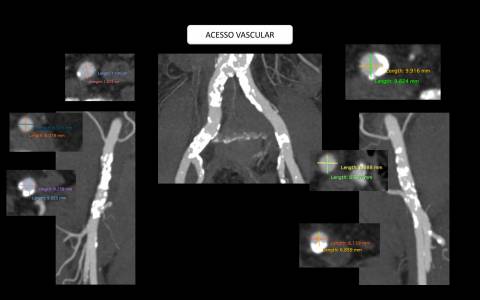

O estudo de angiotomografia evidenciou que as artérias iliacas externas e femorais apresentavam-se com muitas calcificações e ponto de estenose mais crítica em artéria ilíaca comum direita. Diante dos achados de imagem, foi optado por endoprotese de aorta abdominal de baixo perfil (Incraft – Cordis).